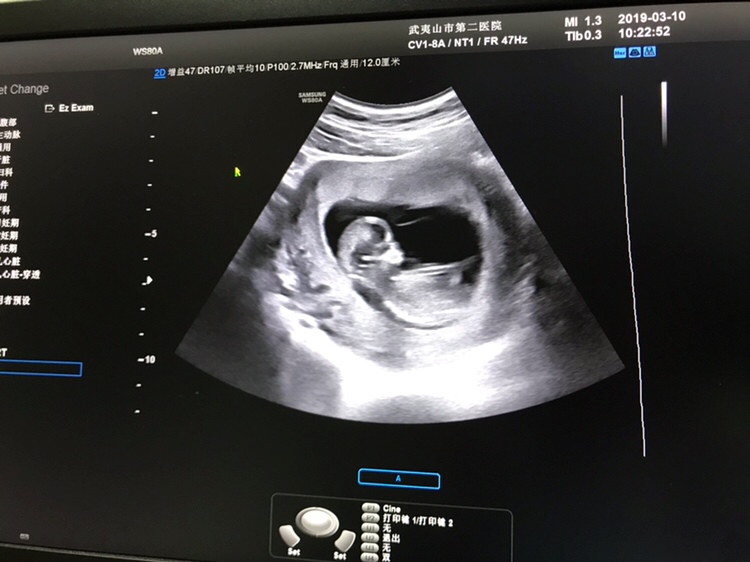

孕16周+4天

B超是要看屁股部位有没有小🐔,这个图片看不到屁股!